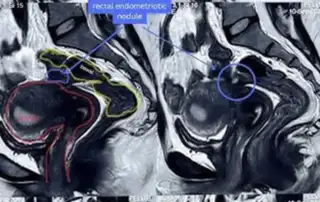

DOI: 10.36205/trocar7.2026008 - Real-Time Surgical Guidance with Robotic-Integrated Intraoperative Ultrasound in Bowel Endometriosis: A Two-Case Experience

Anshuma Shukla Kulkarni, Anushka Mehta, Riyanshi Thakur

DOI: 10.36205/trocar7.2026009 - Early Laparoscopic Excision of a Non-Communicating Rudimentary Horn Pregnancy Conceived via Transcoelomic Migration: A Video Report